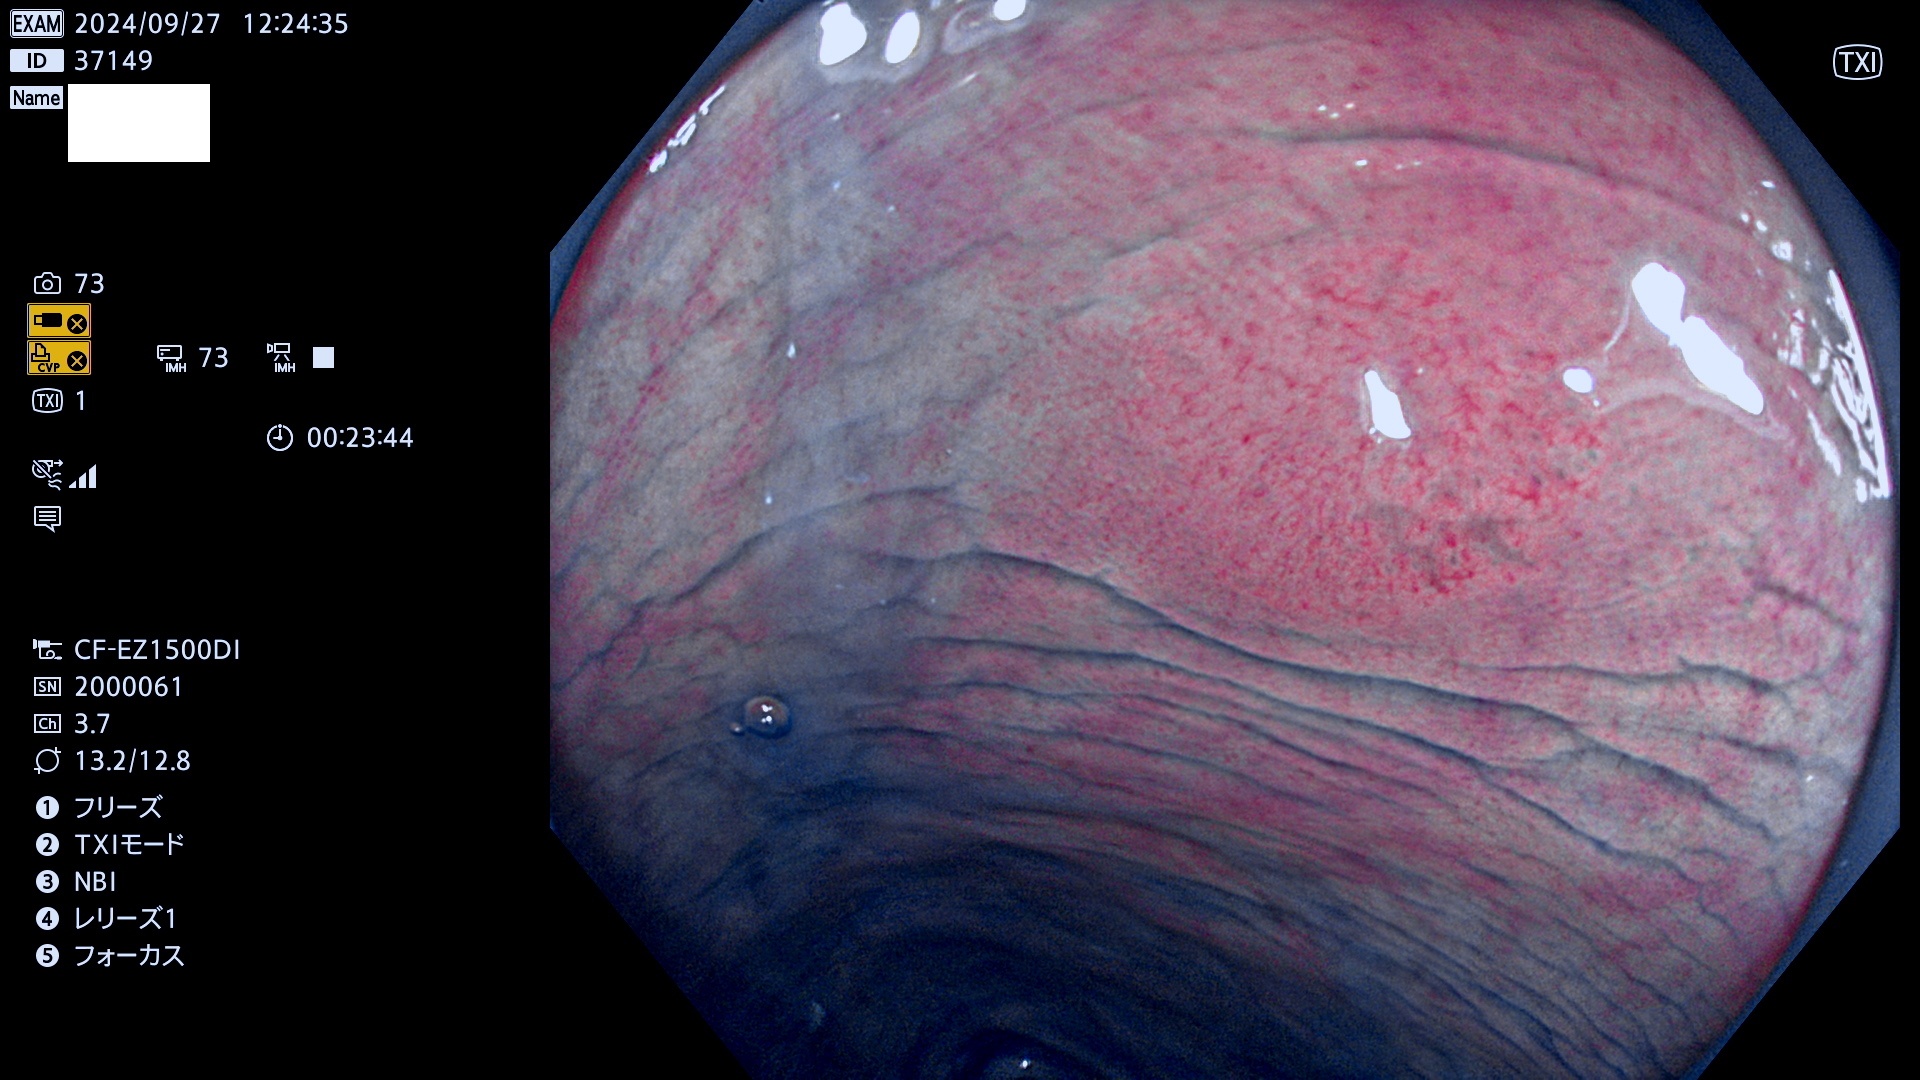

今週のUb、Uc型腺腫

完全に平坦な物をUb、陥凹している物をUcと呼びます。最も発見が難しく危険な病変です。

毎週の検査(木・金・土・日)に発見されたUb、Uc型・腺腫を、その週の日曜の夜にUPし1週間、提示します。

抽出の対象期間 2024年9月26日〜9月29日の4日間(48件の検査)12件 (12/48=25%)